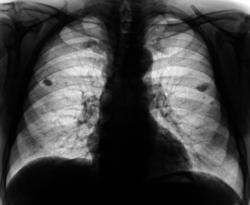

Плотные и обызвествленные очаги различных размеров.

Справа на верхушке плотный обызвествленный очаг.

Плотные и средней интенсивности очаги на верхушках.

Группа плотный очагов слева на уровне 1 межреберья.